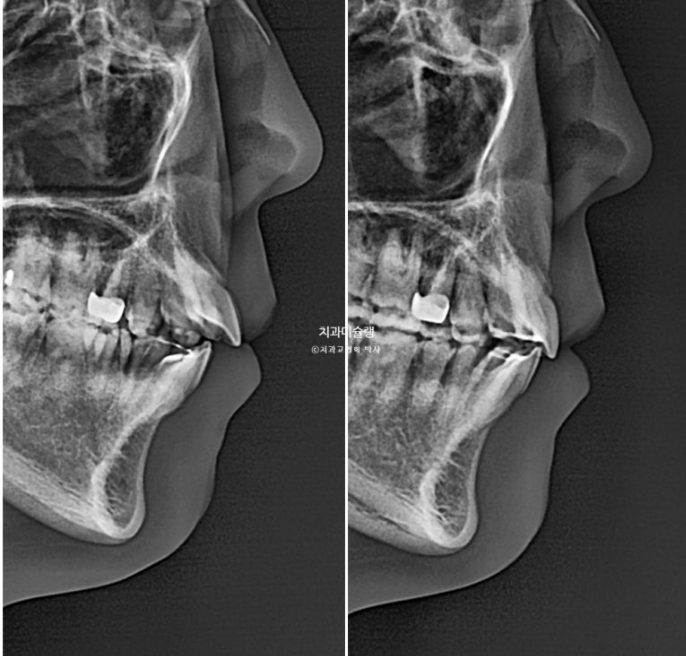

안모에서는 입술에 힘을 빼면 살짝 벌어지는 입술부전증이 보입니다.

24.06

원인은 위 앞니 돌출 때문입니다.

치료계획은 비발치로 사랑니 공간으로 어금니들을 뒤로 밀어 돌출을 해소하고 개방교합, 가위교합 등을 개선하기로 합니다.

24.06~25.11

윗니 아랫니 수평 간격이 줄어들며 입술부전증이 해소가 되었습니다.

윗니 뻗침이 줄어들어 아랫니 간격이 줄어들며 입술이 자연스럽게 다물리게 되었습니다